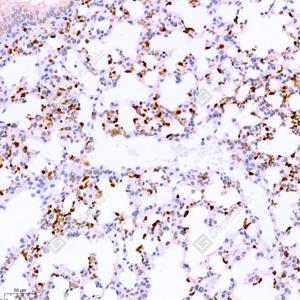

IHC检测CD11b蛋白(货号 GB11058). 样品: 小鼠肺炎(LPS), 4%多聚甲醛 (货号G1101) 固定12-24小时. 抗原修复: 柠檬酸抗原修复液(干粉, pH 6.0) (G1201), 98℃, 20分钟. —抗: 1: 500稀释, 4℃ 孵育过夜. 二抗: HRP标记山羊抗兔IgG (H+L) (货号GB23303), 1: 200稀释, 室温孵育1小时. |

IHC检测CD11b蛋白(货号 GB11058). 样品: 大鼠肺炎(LPS), 4%多聚甲醛 (货号G1101) 固定12-24小时. 抗原修复: 柠檬酸抗原修复液(干粉, pH 6.0) (G1201), 98℃, 20分钟. —抗: 1: 500稀释, 4℃ 孵育过夜. 二抗: HRP标记山羊抗兔IgG (H+L) (货号GB23303), 1: 200稀释, 室温孵育1小时. |